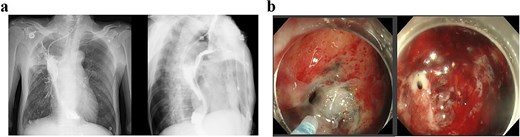

The patient received two cycles of albumin-bound paclitaxel and cisplatin chemotherapy on Day 52 and Day 76. Following the second cycle, he developed recurrent high-grade fever with productive cough. Laboratory tests revealed elevated inflammatory markers, and chest CT demonstrated severe pulmonary infection unresponsive to antibiotic therapy. Subsequent upper gastrointestinal imaging identified an esophagogastrobronchial fistula (Fig. 3a). Endoscopy revealed a 2 cm necrotic gastric wall defect distal to the anastomosis, accompanied by thickened visceral pleura and a fistulous tract connecting the right lung to the gastric lumen (Fig. 3b). Given the extensive defect and absence of intrathoracic infection, conservative measures, including fasting, gastric decompression, and nutritional support, were initiated.

(a) Upper gastrointestinal series obtained 2 months postoperatively. (b) Gastroscopic examination performed 2 months postoperatively.